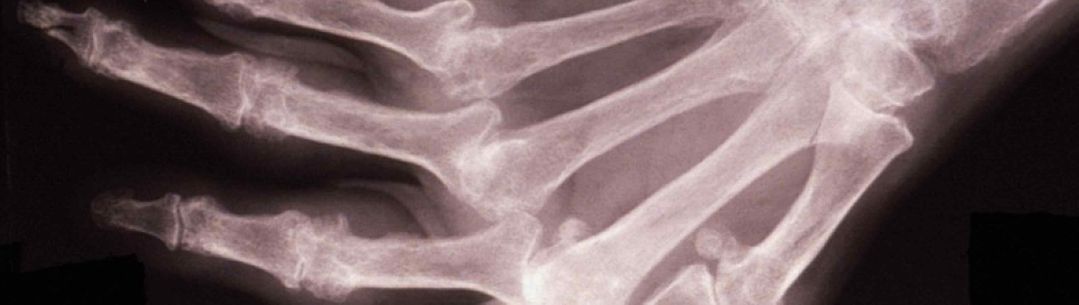

Rheumatoid arthritis (RA) is a costly and debilitating autoimmune disorder that is characterized by joint pain, stiffness, and impaired functionality. Work at Imperial College identified tumour necrosis factor (TNF) as a key therapeutic target in the abnormal joint lining in RA. It established the concept of biological therapy demonstrating the use of an antibody to block a cytokine and treat chronic inflammatory disease. In 2012 Remicade® was the 4th best-selling worldwide drug with total global sales of $7.67 Billion.